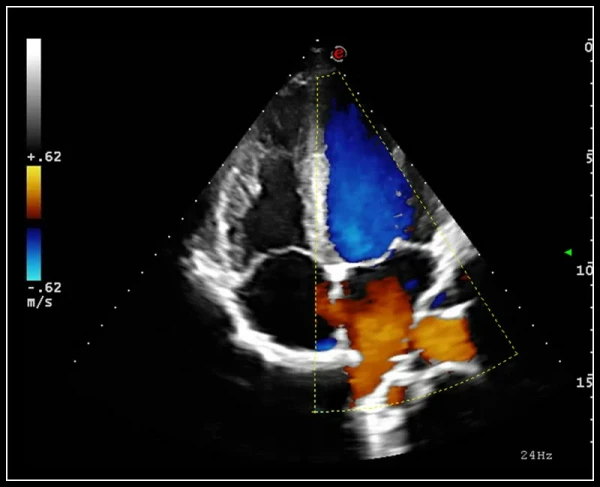

ULTRA-Color Doppler rangli xaritalash usullari: yuqori sezuvchanlik, chuqur kirish va yuqori aniqlik

EasyTrace algoritmi. Doppler rejimlarida vizualizatsiyani avtomatik sozlash algoritmi, aks ettirish burchagini to'g'rilaydi va bir necha soniya ichida miqdoriy ma'lumotlarni taqdim etadi.